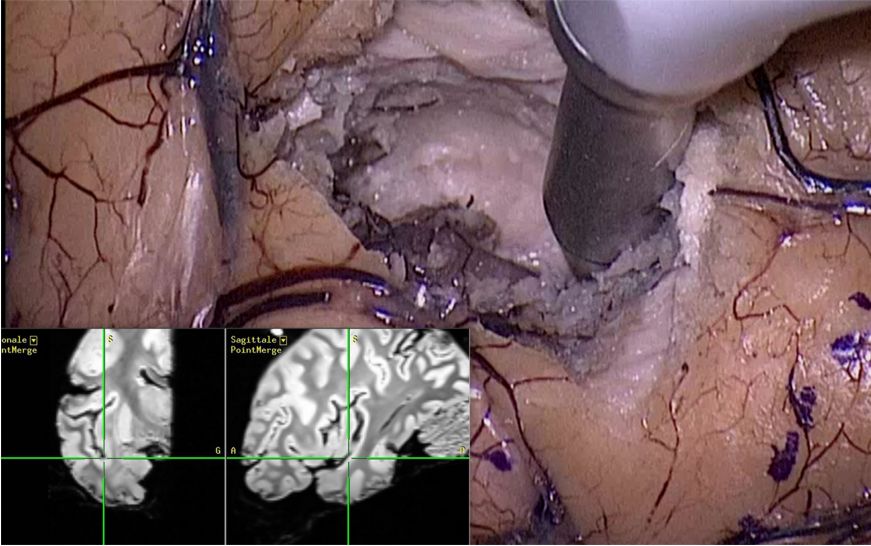

将内镜置于颞极,调整内镜方向,为到达岛叶后部提供一个良好的视角(图4、5)。

图4. 操作岛叶后部时的内镜和吸引器的位置;内镜头端位于颞极,指向岛叶后部。A.全图观;B.局部观。

使用两把改良后不同长度和角度的“S”形吸引器,可以实现后岛叶完全切除,到达岛沟上部,即岛后点水平部(图7)。

图7. 神经导航指向岛后点的内镜下观察。